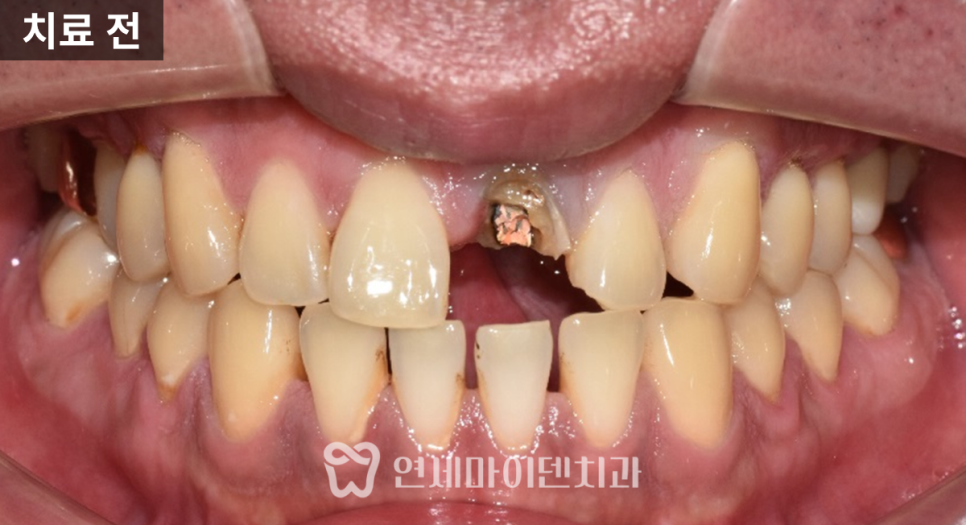

이번 케이스는 통증이 아니라

심미적인 이유로 내원한 경우입니다.

10년 전 신경치료를 받은 앞니

변색이 생겨서 불편함을 호소하셨고,

통증은 없는 상태였습니다.

치아를 확인해보니

크라운 치료는 되어 있지 않았습니다.

외형상 라미네이트로 보이는 경계가 있었고,

잇몸 하방까지 변색이 관찰되었습니다.

입천장 쪽에는

과거 레진으로 크게 수복한 흔적이 있었고

전체적으로 내부 구조가 불안정해 보였습니다.

방사선 사진에서는

뿌리 끝에 가벼운 염증 소견이 확인되었습니다.

신경치료가 완벽해 보이지는 않았기 때문에

단순 미백이 아닌

재신경치료 가능성을 먼저 고려했습니다.